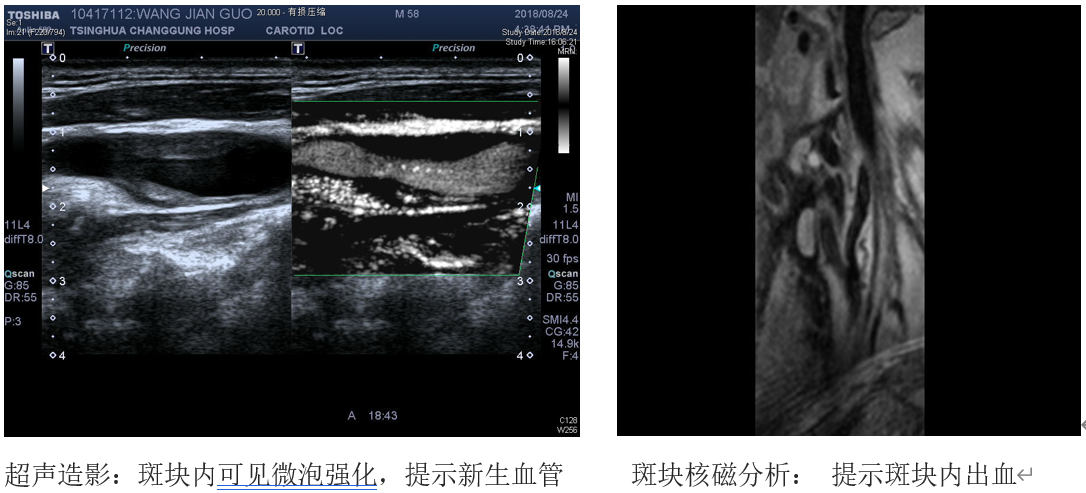

如果斑块增大到一定程度,就要及时行斑块稳定性评估,如果超声造影提示:斑块内有大量新生血管形成,斑块纤维帽不完整;斑块高分辨核磁分析提示:斑块内出血及存在大的脂类核心、纤维帽破裂等情况,说明斑块极不稳定,脱落导致远端脑梗塞风险较大。